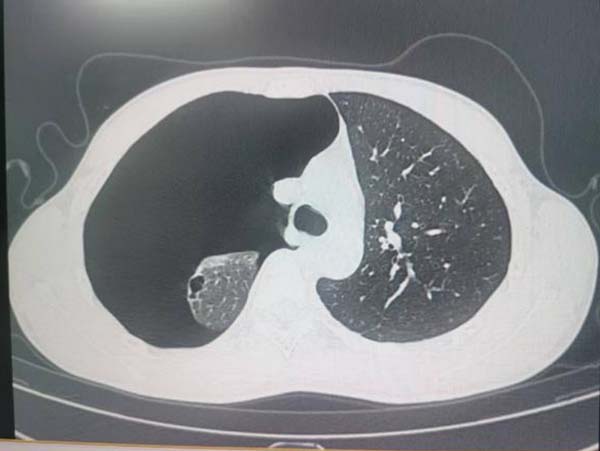

此两例患者一例为18岁在校大学生、另一例为25岁公司白领,均于运动后感胸闷胸痛,伴呼吸困难。至我院外科急诊就诊,胸CT检查示:气胸,肺大泡。收住院后,外科团队在手术室麻醉科的全力配合下,为患者成功行胸腔镜下肺楔形切除术,术后患者顺利出院,尽快回归到学习工作中。

图1 术前胸部CT